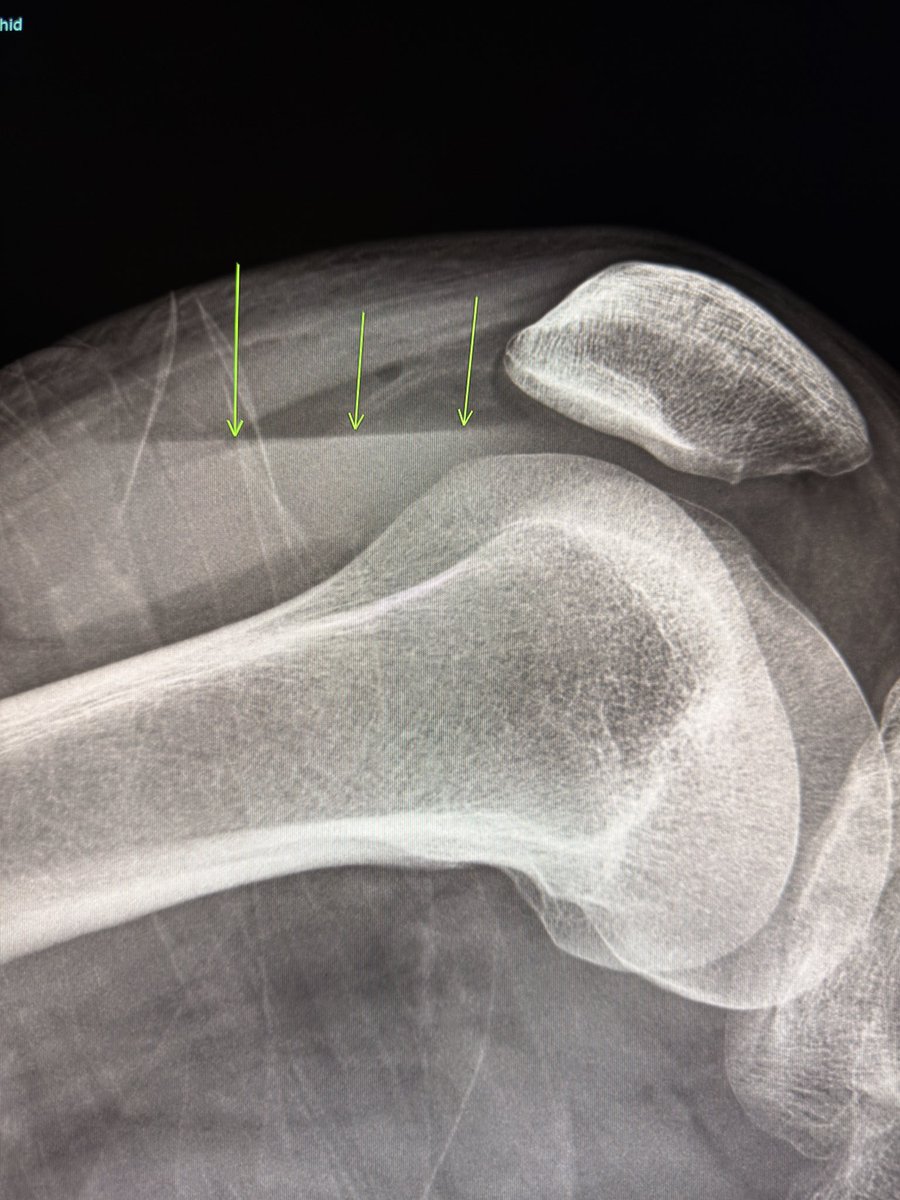

A large dorsal talar beak on sagittal CT or lateral ankle radiograph.

Talar beak is a marker of restricted subtalar motion, not a diagnosis. In a young patient, actively search for a subtalar coalition.

Wisdom: A talar beak should trigger a search, not end it.